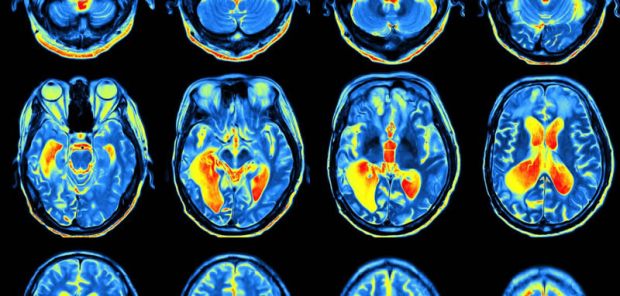

A UCLA-led study has found that MRI scans can help doctors distinguish whether a person’s memory loss is being caused by Alzheimer’s disease or by traumatic brain injury.